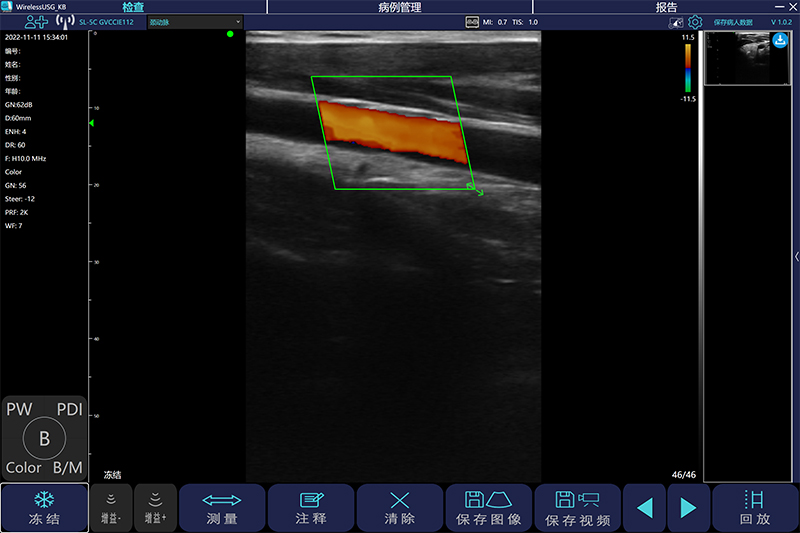

超声在血管外科中的应用

作者:杨宝钟[1]单位:北京中医药大学东方医院[1] 超声作为一种无创检查方法,已经广泛用于血管外科。它不仅可以显示病变部位,还可以显示病变范围,病变与周围器官的关系、···